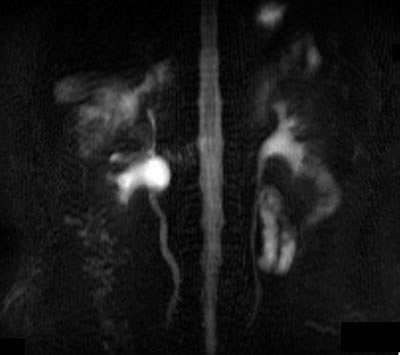

МРТ |

|

МРТ – регионарные лимфоузлы

увеличены до 15-17 мм в диаметре, в желчном пузыре

несколько камней с максимальным размером 6-7 мм